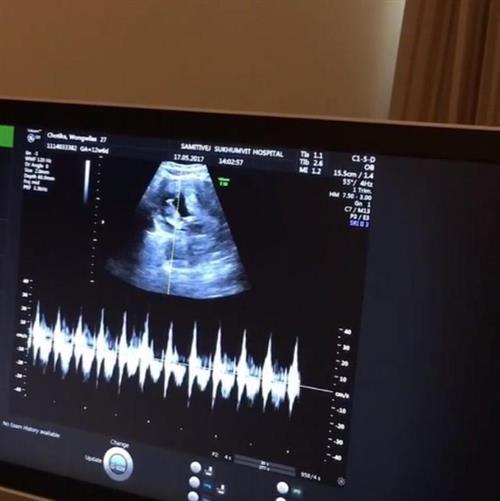

ថៃ ៖ ដោយសារតែមានការងារជាច្រើនខាងផ្នែកវិស័យសិល្បៈ ទើបធ្វើឲ្យតារាសម្តែងស្រីចិត្តអាក្រក់ នាង Noey chotika ធ្លាប់បានប្រកាសប្រាប់អ្នកកាសែតថា នាងនឹងពន្យារពេលយកកូនសិន ប៉ុន្តែប្រភពផ្លូវការរបស់ប្រទេសថៃបានចុះផ្សាយ កាលពីពេលថ្ងៃទី ២៤ ខែឧសភានេះថា តួស្រីក្នុងរឿង បុផ្ផាលាក់លម្អង រូបនេះកំពុងតែមានផ្ទៃពោះចំនួន ១៣ សប្តាហ៍ទៅហើយ ។

លោក Arm Maneechy ដែលជាស្វាមីសេដ្ឋីរបស់នាង Noey chotika ក៏បានសម្តែងអារម្មណ៍សប្បាយរីករាយយ៉ាងក្រៃលែង ចំពោះដំណឹងល្អមួយនេះ ។ ទោះបីជាយ៉ាងណាក៏ដោយចុះ ប្រភពដដែលនៅមិនទាន់អាចបញ្ជាក់បានទេថា កូននៅក្នុងផ្ទៃរបស់តារាថៃរូបនេះ គឺជាកូនប្រុសឬស្រីនៅឡើយទេ ប៉ុន្តែស្វាមីរបស់នាងគឺចង់បានកូនប្រុសដំបូងសិន ៕